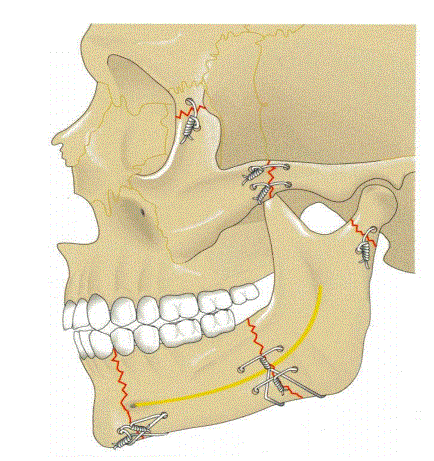

Le Fort 1-3 , grob Frakturverläufe erklären

How well did you know this?